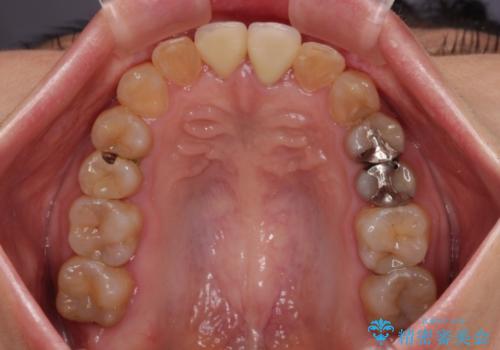

前歯のデコボコをワイヤー矯正できれいに整える

舌の突出癖により治療期間中に開咬となり、治療が長引きましたが、口元も治療前よりも引っ込めることができ、すっきりとした仕上がりとなりました。

気になっていた前歯の変色も、矯正治療後にオールセラミッククラウンにて補綴治療を行うこととしました。